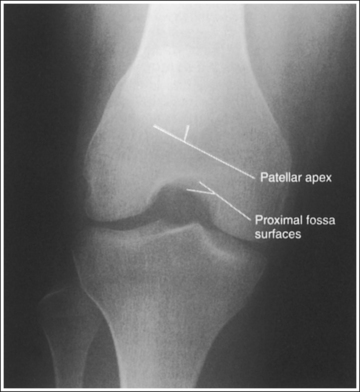

The knee demonstrates an AP projection. The medial and lateral femoral epicondyles are in profile, the femoral condyles are symmetrical, the intercondylar eminence is centered within the intercondylar fossa, and the tibia is superimposed over 0.25 inch (0.6 cm) of the fibular head.

• Effect of rotation. If the femoral epicondyles are not positioned parallel with the IR, an AP projection has not been obtained. If the patient's leg was not internally rotated enough to place the epicondyles at equal distances from the IR, they are not in profile, the medial femoral condyle appears larger than the lateral condyle, and the tibia is superimposed over more than 0.25 inch (0.6 cm) of the fibular head (see Image 54). If the patient's leg was internally rotated more than needed to place the femoral epicondyles at equal distances from the IR, the epicondyles are not demonstrated in profile, the lateral femoral condyle appears larger than the medial condyle, and the tibia is superimposed over less than 0.25 inch (0.6 cm) of the fibular head (see Image 55).

• Analysis of joint space narrowing. On an AP knee projection with adequate positioning, joint space narrowing is evaluated by measuring the medial and lateral aspects of the knee joint, which are also referred to as compartments. The measurement of each of these compartments is obtained by determining the distance between the most distal femoral condylar surface and the posterior condylar margin of the tibia on each side. Comparison of these measurements with each other, with measurements from previous images, or with measurements of the other knee determines joint space narrowing or a valgus or varus deformity. In a valgus deformity the lateral compartment is narrower than the medial compartment; in a varus deformity the medial compartment is narrower (see Images 56 and 57). Precise measurements of the compartments are necessary to ensure early detection of joint space narrowing and are best obtained when the knee joint space is completely open. If an inaccurate central ray angulation was used for an AP knee projection, the knee joint is narrowed or obscured, the intercondylar eminence and tubercles are foreshortened, and the tibial plateau is demonstrated.

• Center the central ray to the midline of the knee at a level 1 inch (2.5 cm) distal to the palpable medial epicondyle to place the knee joint in the center of the exposure field. (As long as the knee remains extended, an alternative central ray placement is 0.5 inch (1.25 cm) distal to the patellar apex.) Open the longitudinal collimation enough to include one fourth of the distal femur and proximal lower leg. Transverse collimation should be to within 0.5 inch (1.25 cm) of the knee skin line.